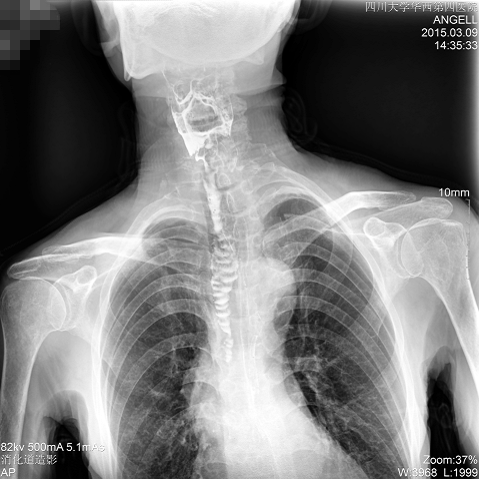

如下圖所示:該患者因吞咽時感到很難受,進食時也經常咳嗽故就醫診斷。使用多功能dr為病人進行消化道造影診斷,要求他吞鋇后發現,食道各段通過順利,形態規則,雙側梨狀窩不對稱左側稍淺,多次吞咽動作后,仍見鋇劑滯留,并見鋇劑進入氣管,屬于會厭征陽性。會厭功能紊亂,鋇劑進入了氣管。

圖為斜位:通過動態影像可以清楚看到鋇劑進入了支氣管道

通過多功能dr可以診斷該病人的癥狀為會厭功能紊亂,鋇劑進入到了氣管。而在動態透視下可以清晰的觀察到鋇劑從何處進入氣管,可清晰顯示食管粘膜結構。使用多功能dr其獨特的視頻采集技術,可實時保存視頻并能實現900萬像素實時點片,才能獲取這樣清晰的病灶點。而常規dr只能拍攝靜態片,且成像效果大打折扣,因此較難確診病灶。